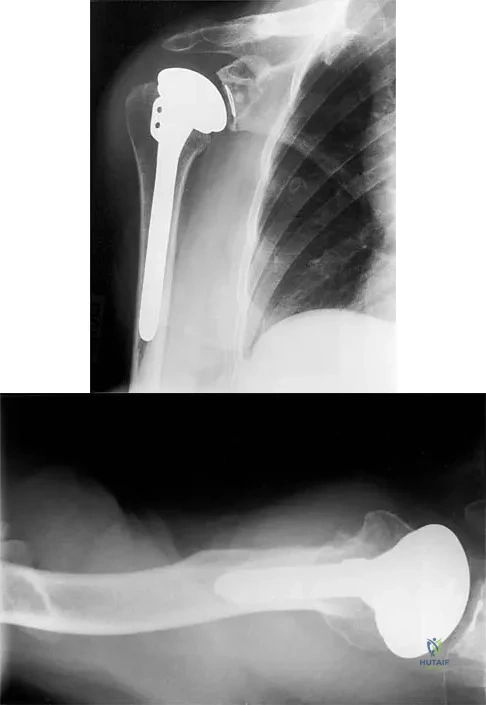

A 54-year-old man undergoes total shoulder arthroplasty for osteoarthritis. Despite compliance with an early passive range-of-motion exercise program, he does not regain more than 90 degrees of elevation, 10 degrees of external rotation, and has internal rotation to the fifth lumbar vertebra. At 6 months, his motion fails to improve. Radiographs are shown in Figures 18a and 18b. What is the best course of action?

Explanation